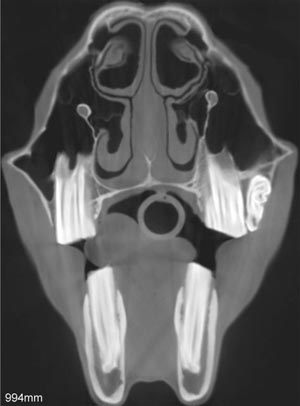

Palatoschisis is the technical term for cleft palate [schist- = split as in schistosomus reflexus]. Cleft palates can be unilateral or bilateral. The bilateral type is symmetrical and the ventral edge of the nasal septum is easily seen. In the unilateral type the ventral edge of the nasal septum is fused to the normal side hard palate so that it is hard to see.

Bilateral cleft palate is more common than unilateral and unilateral is usually associated with incomplete clefts and cleft lip (hare lip because it resembles the upper lip of a hare). In animals cleft palate is far more common than cleft lip (cheiloschisis). The University of Minnesota museum collection has 19 cleft palate specimens but only 3 of them have a cleft lip. Cleft palate may occur associated with other defects such as dicephalus or achondroplasia or it may not be associated with other defects. In our collection 8 of 19 cleft palates were associated with other defects.

The Kentucky study of equine congenital defects found 24 cases of cleft palate in 608 foals with defects (AJVR 46:353-358, 1985). In contrast, a multispecies study of congenital defects found only 40 cleft palates among 6,455 animals with congenital defects (AJVR 31:1871-1879, 1970).